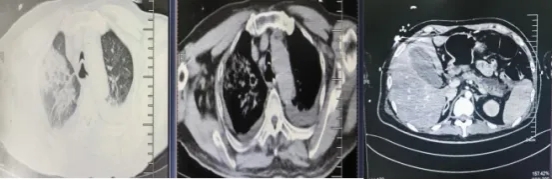

经过17个日夜的全力救治,薛先生的生命体征逐渐平稳,神志转清,成功脱离了呼吸机支持,血氧饱和度稳定在98%以上。后续复查显示,其胰腺周围渗出明显吸收,肺部感染情况大幅好转,腹腔积液显著减少。